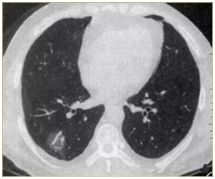

肺部小結(jié)節(jié)通常是指影像檢查(X線或者CT)中發(fā)現(xiàn)的直徑≤2cm的類圓形病灶,≤3cm的稱為結(jié)節(jié),>3cm的稱為腫塊。

也有學(xué)者認(rèn)為,分得太細(xì)并無(wú)意義,例如2.2cm的結(jié)節(jié)與1.9cm的小結(jié)節(jié),臨床上并沒(méi)有本質(zhì)的區(qū)別。在這里我們統(tǒng)一把≤3cm的結(jié)節(jié)統(tǒng)稱為肺部小結(jié)節(jié),在肺部小結(jié)節(jié)中,60%—70%為良性結(jié)節(jié),30%—40%的結(jié)節(jié)方為惡性結(jié)節(jié),所以,發(fā)現(xiàn)肺部小結(jié)節(jié)切勿驚慌。

結(jié)節(jié)的大、小與良、惡性有一定的相關(guān)性,當(dāng)肺部結(jié)節(jié)>3cm的病灶多為惡性,而微小的結(jié)節(jié),良性的可能性居多。

我們常看到的影像學(xué)描述中的“磨玻璃結(jié)節(jié)(GGO)”,其中一部分是非典型腺瘤樣增生(AAH)或原位腺癌(AIS),結(jié)節(jié)內(nèi)部的實(shí)變與生長(zhǎng)速度的加快(范圍變大)常意味病變性質(zhì)的轉(zhuǎn)變,可以逐步演變?yōu)槲⒔?rùn)腺癌(MIS)、浸潤(rùn)性腺癌(IAC)。